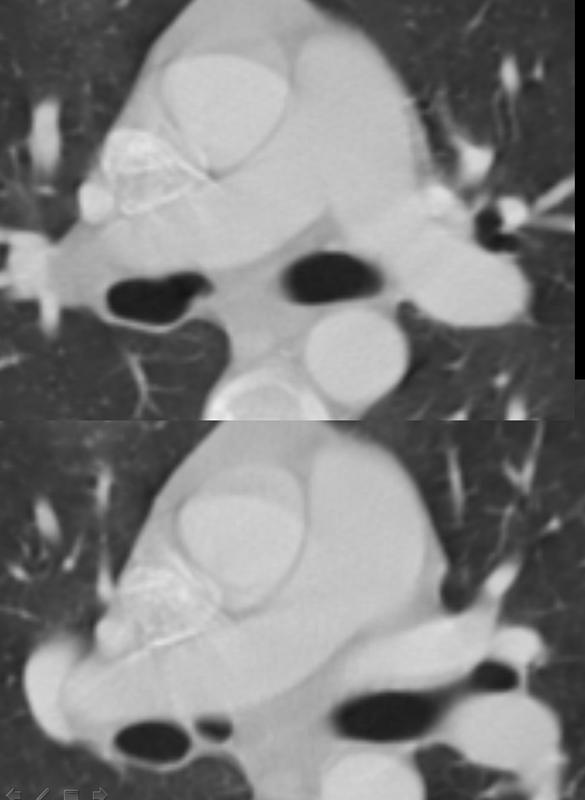

Gallery Congenital cardiac bronchus axial

cardiac bronchus axial